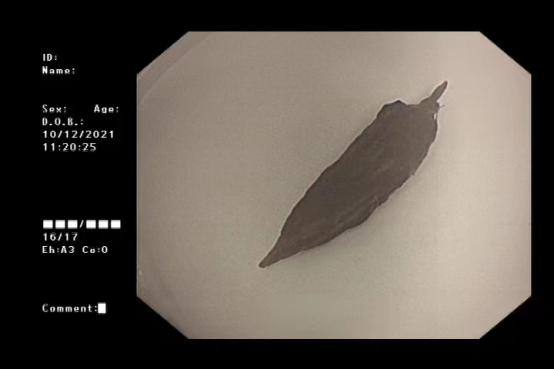

孙德荣立即请胸外科副主任医师张凯、麻醉科高大鹏等医生开展多学科会诊,与患者家属沟通后,制定了详细手术方案。枣核两端尖锐部分已深深扎入到食管粘膜内,要想顺利取出难度非常大。消化内镜团队分析情况并做好预案,谨慎操作下,终于将枣核取出。其中一处破溃口已经穿孔,为有助后期恢复,医生在吕先生胃内放置鼻饲管。吕先生看见被取出的枣核,非常惊讶:“吃大枣时根本没感觉到把枣核吃进去了,差点要了命!”